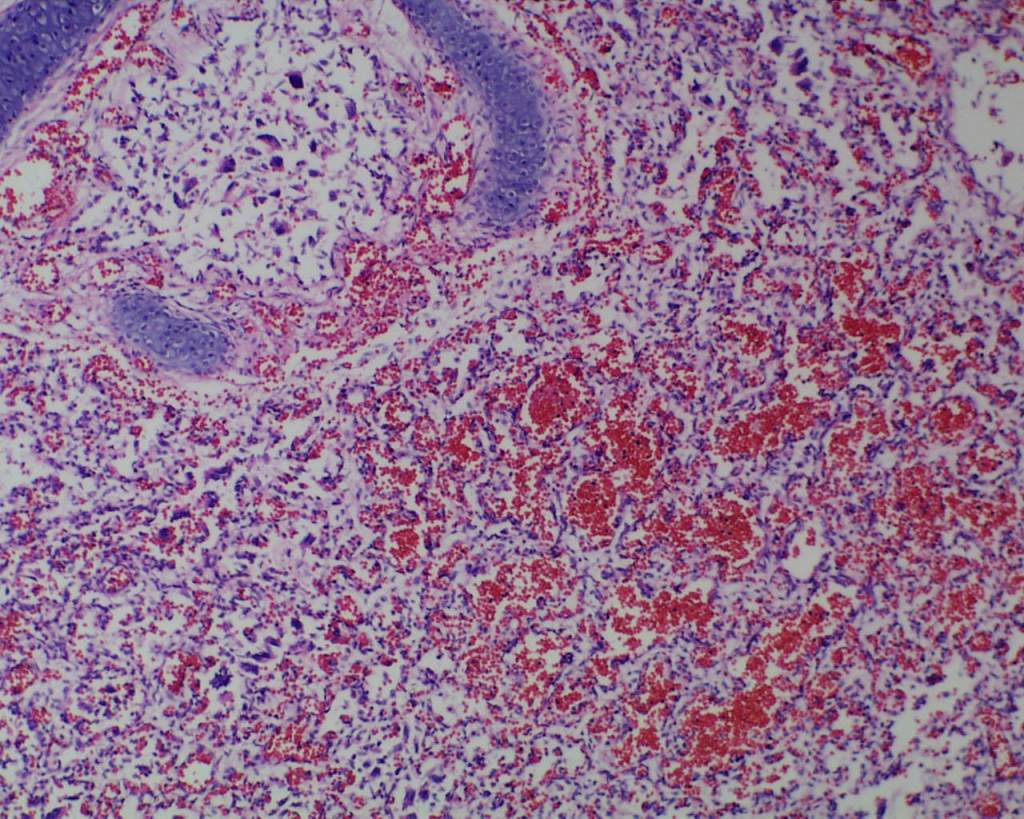

Color: The normal lung is pink. In the stillborn infant, it may be red from hemoglobin staining from autolysis or from vascular congestion, or rarely pneumonitis. Petechiae of the visceral pleura may be present. The significance of the petechiae is discussed in the section on thymus. If the fetus is anemic, the lungs will be paler than normal. With bacterial overgrowth there may be visible foci of gaseous expansion on the surface. Foci of pneumonitis or deep hemorrhage may be seen on the surface.

Beside hemorrhage in the visceral pleura, there may be deeper connective tissue interstitial hemorrhage in the lung. The capillaries in other areas of the lung with pleural petechiae are often engorged as well, and the rigors of gasping and pressure change may account for deeper hemorrhages (Fig 20a, b).

Focal hemorrhages may also be found in the airways usually with evidence of hemorrhages in other organs suggestive of disseminated intravascular coagulation and shock (Fig 21).